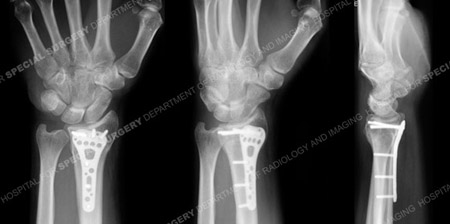

Postoperative anteroposterior, mortise and lateral radiographs at 6 months illustrate a healed distal radius fracture in excellent alignment.